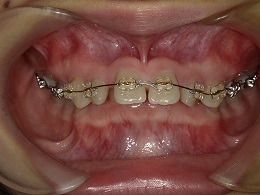

治療中正面

お試し矯正後、深い噛み合わせ改善のため上下全体矯正中の患者様の症例になります。